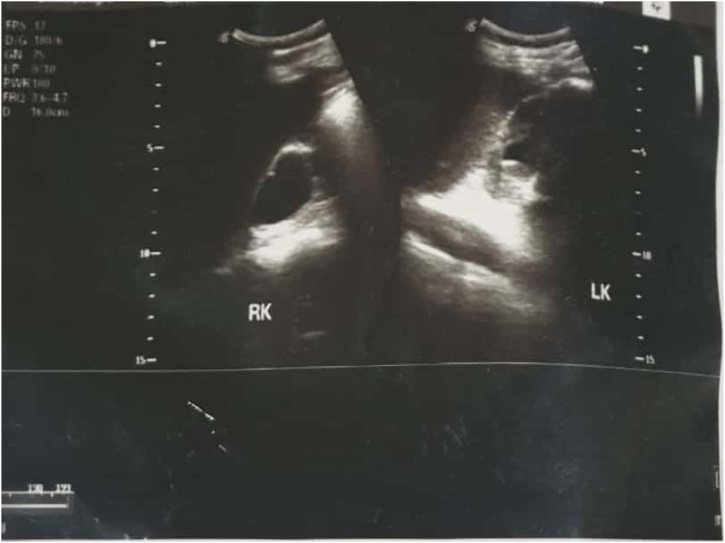

On physical examination, it showed an abdominal mass, in the suprapubic region with size of 20cm × 10cm. The mass is solid, round, distinct border, mobile, and without tenderness in palpation. No prostate enlargement was found on digital rectal examination. Urine examination showed signs of hematuria. There is radioopaque lesion in the bladder region on the plain abdominal radiograph. The lesion is round, single, large, occupies the entire bladder (Fig. 1). It was most likely to be a giant bladder stone. The ultrasound examination of the kidney revealed severe right hydronephrosis, and moderate left hydronephrosis (Fig. 2). Laboratory assessment shows impaired kidney function test.

Fig. 2.

Ultrasound examination revealed bilateral hydronephrosis (severe hydronephrosis of the right kidney; and moderate hydronephrosis of the left kidney). RK: Right Kidney; LK: Left Kidney.